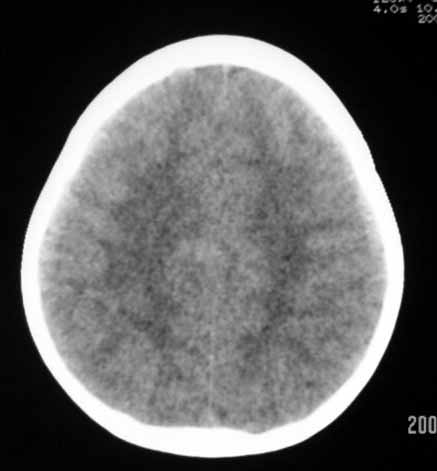

以下是引用why7912在2007-9-1 13:29:00的发言:[br]右侧颞部硬膜外血肿,左侧颞底蛛网膜囊肿,建议观察骨窗

以下是引用wqs571018在2007-9-1 14:57:00的发言:[br]右侧颞部硬膜外血肿,左侧颞底蛛网膜囊肿。